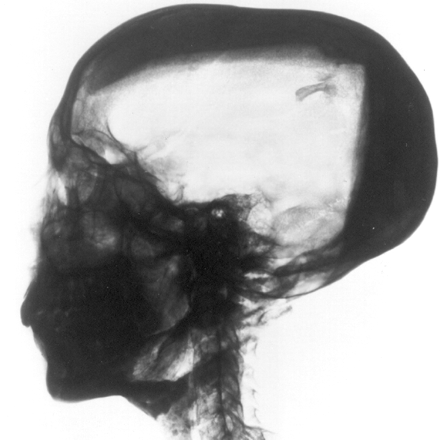

Покажано лицето на Тутанкамон

This CT scan reveals the deformed foot, broken knee, buck teeth, and elongated skull of King Tut.

Photograph courtesy the Supreme Council of Antiquities, Egypt, and National Geographic